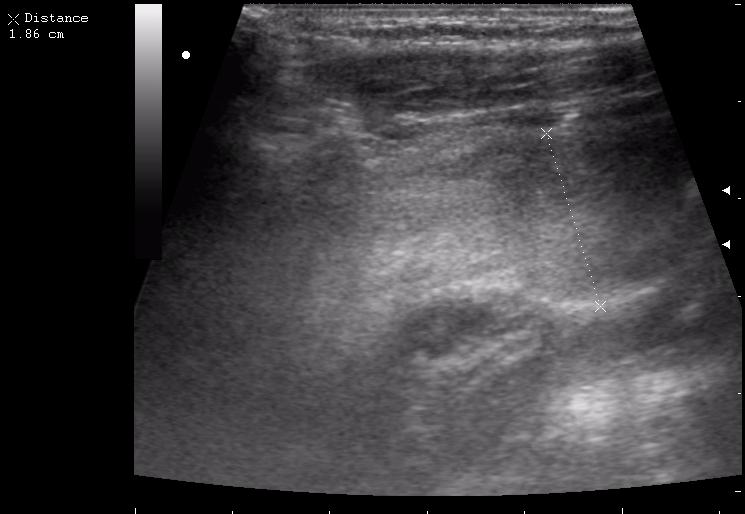

наезд большой черной Прады на маленькую (13кг) 5-летнюю девочку.

получает Медаксон, рабочая версия - изменение желчного пузыря вследствии травмы (шепотом - рекомендация хирургу сменить антибиотик)

сегодня был селезёночный день.